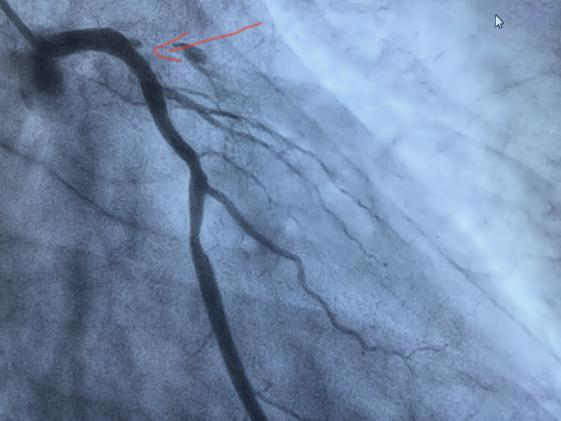

手术前

手术后